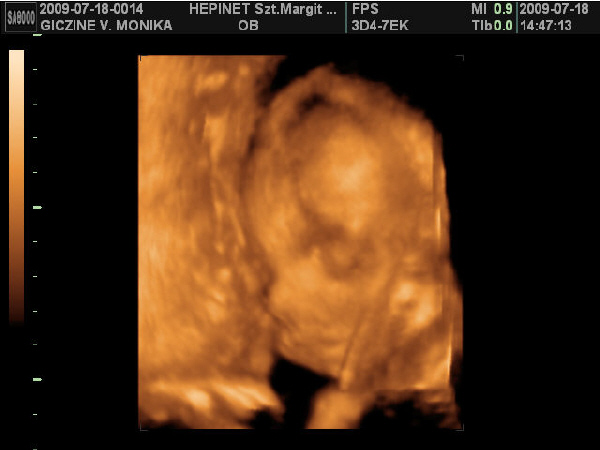

Lányok hoztam nektek képeket: :D :D

Kép

Ezek a képek szombaton készűltek. Bár nehéz volt jó képeket csinálni Lauráról, mert nagyon a méhlepény felé volt fordúlva. :D

Minden tökéletes vele, kb: 1 kilós már.

Ja!

És nagyon hasonlít a bátyjára. :lol: :lol: :lol: